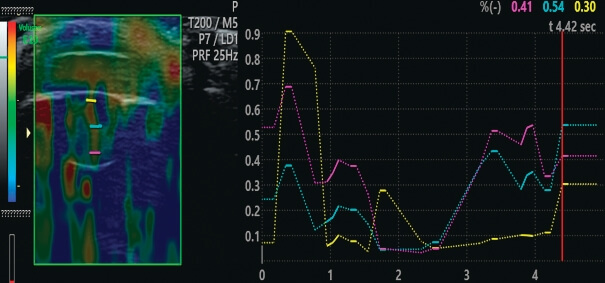

Ультразвуковое обследование в режиме В-сканирования и соноэластографии проводилось для определения показателей упругости и жесткости структур хрусталика. Использовалась многофункциональная ультразвуковая система экспертного класса Volluson E10 (GE Healthcare) с линейным датчиком IL 12–16, работающим на частоте 12–16 МГц.

Акустическая мощность была снижена до безопасного уровня, допустимого в офтальмологии (MI 0,23, TI 1,0) [9]. Исследование выполнялось транспальпебрально, взгляд пациента фиксировался прямо перед собой, сканирование проводилось в аксиальной плоскости. Степень компрессии датчиком контролировалась при помощи шкалы, отображаемой на мониторе прибора. В режиме ELASTO на область роговицы, передней камеры и хрусталика устанавливалась ROI. Далее на полученной эластограмме проводился качественный и количественный анализ жесткости хрусталика. Качественная оценка основывалась на классификации эластотипов (5 эластотипов + BGR), предложенной японскими исследователями A. Itoh и соавт. [10] из университета Tsukuba. Различные цвета использовались для визуализации эластичных и жестких участков хрусталика. Количественная оценка также включала расчет коэффициента жесткости Strain-Ratio (STR). В норме передняя камера и ядро хрусталика отображались на экране монитора в красно-желтой цветовой гамме (рис. 2).

По данным соноэластографии зарегистрировано достоверное снижение показателя передних слоев хрусталика в среднем по группе c 0,68 ± 0,03 до 0,57 ± 0,02 (p < 0,001). Снижение показателя зафиксировано в 56 (97%) глазах, отсутствие динамики — в 2 (3%). Показатель ядра хрусталика достоверно снизился от 0,38 ± 0,01 до 0,32 ± 0,01 (p < 0,001). Снижение показателя зафиксировано в 52 (90%) глазах, отсутствие динамики — в 5 (9%), в одном (1%) случае показатель немного вырос. Показатель задних слоев хрусталика достоверно снизился c 0,51 ± 0,02 до 0,4 1 ± 0,01 (p < 0,001). Снижение показателя зафиксировано в 52 глазах (90%), отсутствие динамики — в 4 (7%), в 2 (3%) глазах показатель немного вырос (рис. 4).